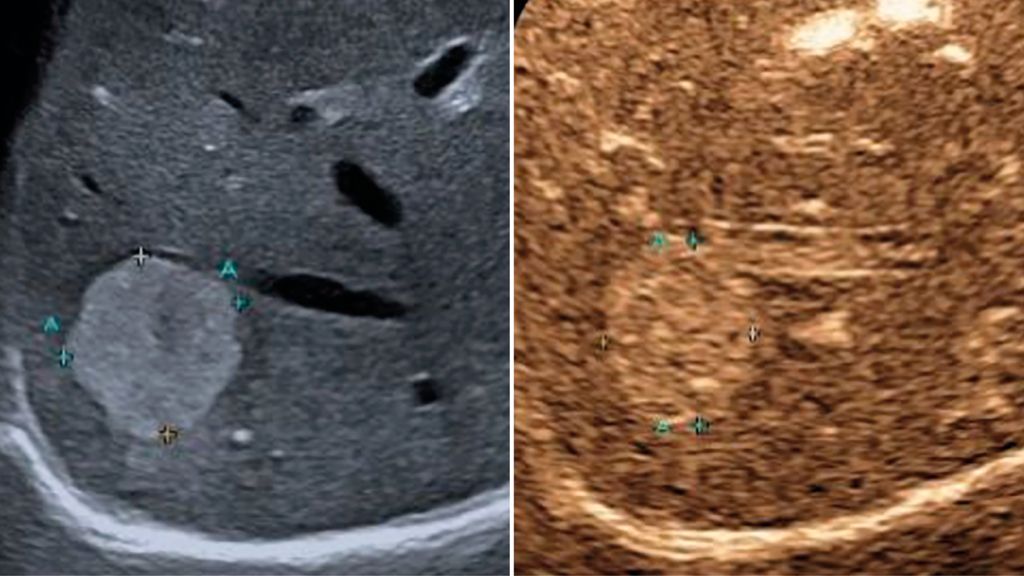

In der früharteriellen Phase zeigen benigne Läsionen wie Hämangiome typische Füllungsmuster ohne «wash-out» in der Portal- oder Spätphase (Abb.1). Maligne Läsionen hingegen weisen meist ein rasches «wash-out» auf und stellen sich in der Spätphase hypokontrastiert dar (Abb.2).3,4

Abb. 1: Typisches Kontrastmittelverhalten eines Hämangioms in der Spätphase mit Hyperenhancement gegenüber dem umgebenden Leberparenchym (rechts)

Abb. 2: Darstellung einer hochgradig Metastasen-suspekten Raumforderung bei Mamma-Neoplasie im linken Leberlappen im B-Bild-Modus (rechts) sowie in der Spätphase nach Gabe von 1,6 ml SonoVue® mit Darstellung eines deutlichen «Wash-out»-Phänomens in der Spätphase 4 Minuten nach Injektion des Kontrastmittels (links)